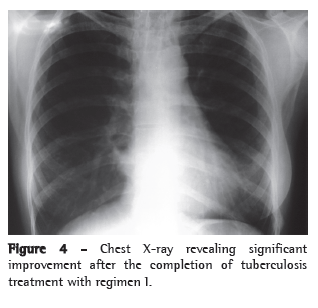

Another TST was performed, and the result was again negative (induration, 0 mm). Two consecutive sputum samples were smear-negative (Ziehl-Neelsen staining). The patient underwent bronchoscopy, which showed a whitish infiltrative lesion occluding 50% of the bronchial lumen of the left upper lobe as well as intense adjacent inflammatory reaction. The anatomopathological examination of the bronchial lesion revealed an extensive, chronic granulomatous inflammatory response with coagulative necrosis. There were no signs of malignancy. The bronchoalveolar lavage fluid tested positive for AFB in smear microscopy. The patient was diagnosed with pulmonary tuberculosis, and treatment with regimen I (rifampin/isoniazid/pyrazinamide) was instituted. She presented favorable evolution, showing improvement in the symptoms and in the radiological aspect thirty days later. The patient was discharged after six months of treatment, showing complete resolution of the respiratory symptoms and significant improvement in the chest X-ray results (Figure 4).